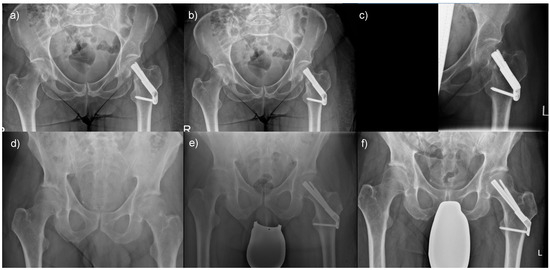

A minority of patients had complications when femoral neck fractures were treated with an FNS. A 67-year-old male patient was transferred to our hospital following a fall from standing height. He had a Pauwels type 2, Garden type 3 fracture (Figure 6a) and was treated with an FNS (Figure 6b). Despite an initially satisfactory follow-up, he presented with a consecutive cutting-out of the implant at six months following surgery (Figure 6c). However, most patients treated with an FNS had a satisfactory outcome. For instance, a 62-year-old male patient presented with a Pauwels type 2, Garden type 2 fracture (Figure 6d) and received an FNS (Figure 6e). The follow-up result was inconspicuous, and the fracture healed (Figure 6f).

Figure 6.

Outcomes of femoral neck fractures when treated with an FNS: (a) A 67-year-old male patient presented with an unstable femoral neck fracture, (b) which was treated with an FNS, but (c) presented with implant cut-out following surgery. In comparison, (d) a 62-year-old male patient presented with a comparable fracture morphology, (e) was treated in the same manner, and (f) had a favorable postoperative outcome.